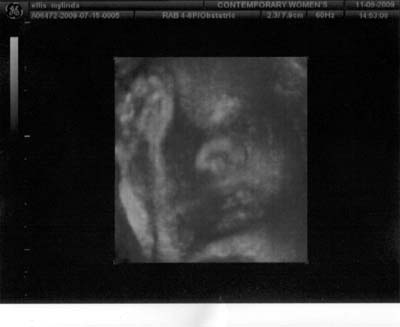

I went to the Dr.'s yesterday and these are the latest photos. I am not a real big fan of the 3D ultra sounds as the baby look alienish but thought I would share them anyway.

How great it is to live in a time where we have all the modern technology to be able to see photos of the unborn babies. He is doing well and weights 4 1⁄2 lbs. He is very active and I'm sure will give me a run for my money. Still don't have a name but I think we will decide when we see him. Hope everyone is doing well. Love ya, Zeke, Mylinda, Lauren and the boy.